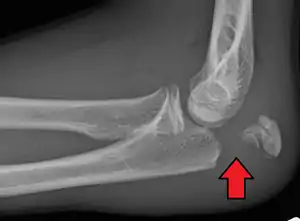

Olecranon fracture

Olecranon fracture is a fracture of the bony portion of the elbow. The injury is fairly common and often occurs following a fall or direct trauma to the elbow. The olecranon is the proximal extremity of the ulna which is articulated with the humerus bone and constitutes a part of the elbow articulation. Its location makes it vulnerable to direct trauma.

To assess an olecranon fracture, a careful skin exam is performed to ensure there is no open fracture. Then a complete neurological exam of the upper limb should be documented.[1][5] Frontal and lateral X-ray views of the elbow are typically done to investigate the possibility of an olecranon fracture.[2] A true lateral x-ray is essential to determine the fracture pattern, degree of displacement, comminution, and the degree of articular involvement.

- Type III: Displaced unstable fracture – In this case, the fracture fragments are displaced and the forearm is unstable in relation to the humerus. It is a fracture -dislocation. It also may be either non-comminuted (Type IIIA) or comminuted (Type IIIB).